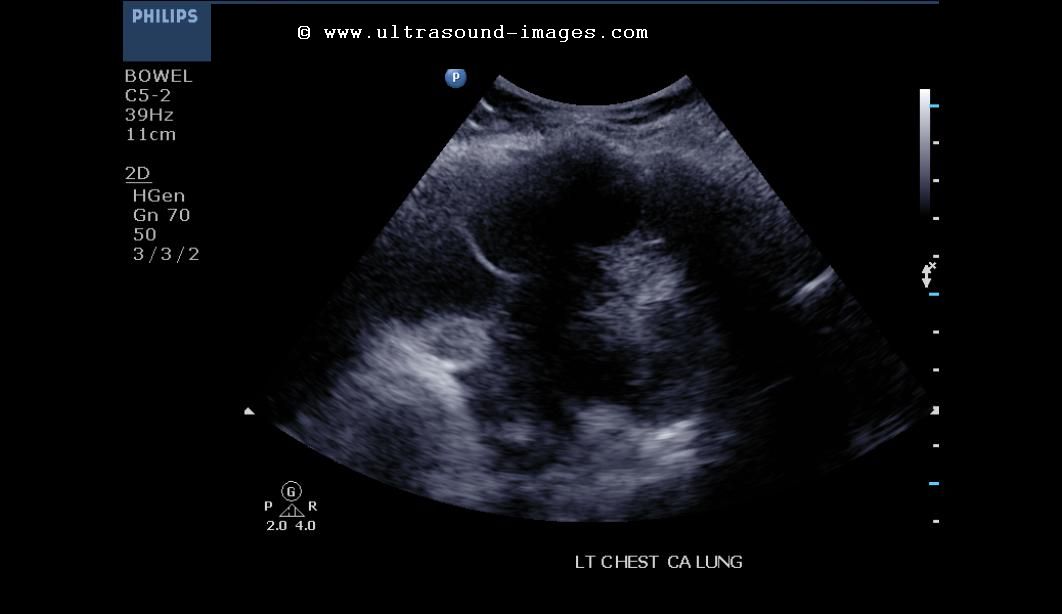

Septate pleural effusion in known Carcinoma lung

This is an elderly female patient and a known case of carcinoma left lung. Left lower zone pleural effusion is seen in these ultrasound images of left hemi-thorax.

Medical literature classifies pleural effusion based on sonographic patterns as:

1) anechoic

2) complex septated

3) complex nonseptated

4) homogenous

Studies have been done to evaluate effusion in lung cancer and also in tuberculous lung infections.

In this case the pleural effusion is certainly the exudative type rather than transudate variety. Complex septate effusions are more common in tubcerculosis but are also seen in lung malignancy.